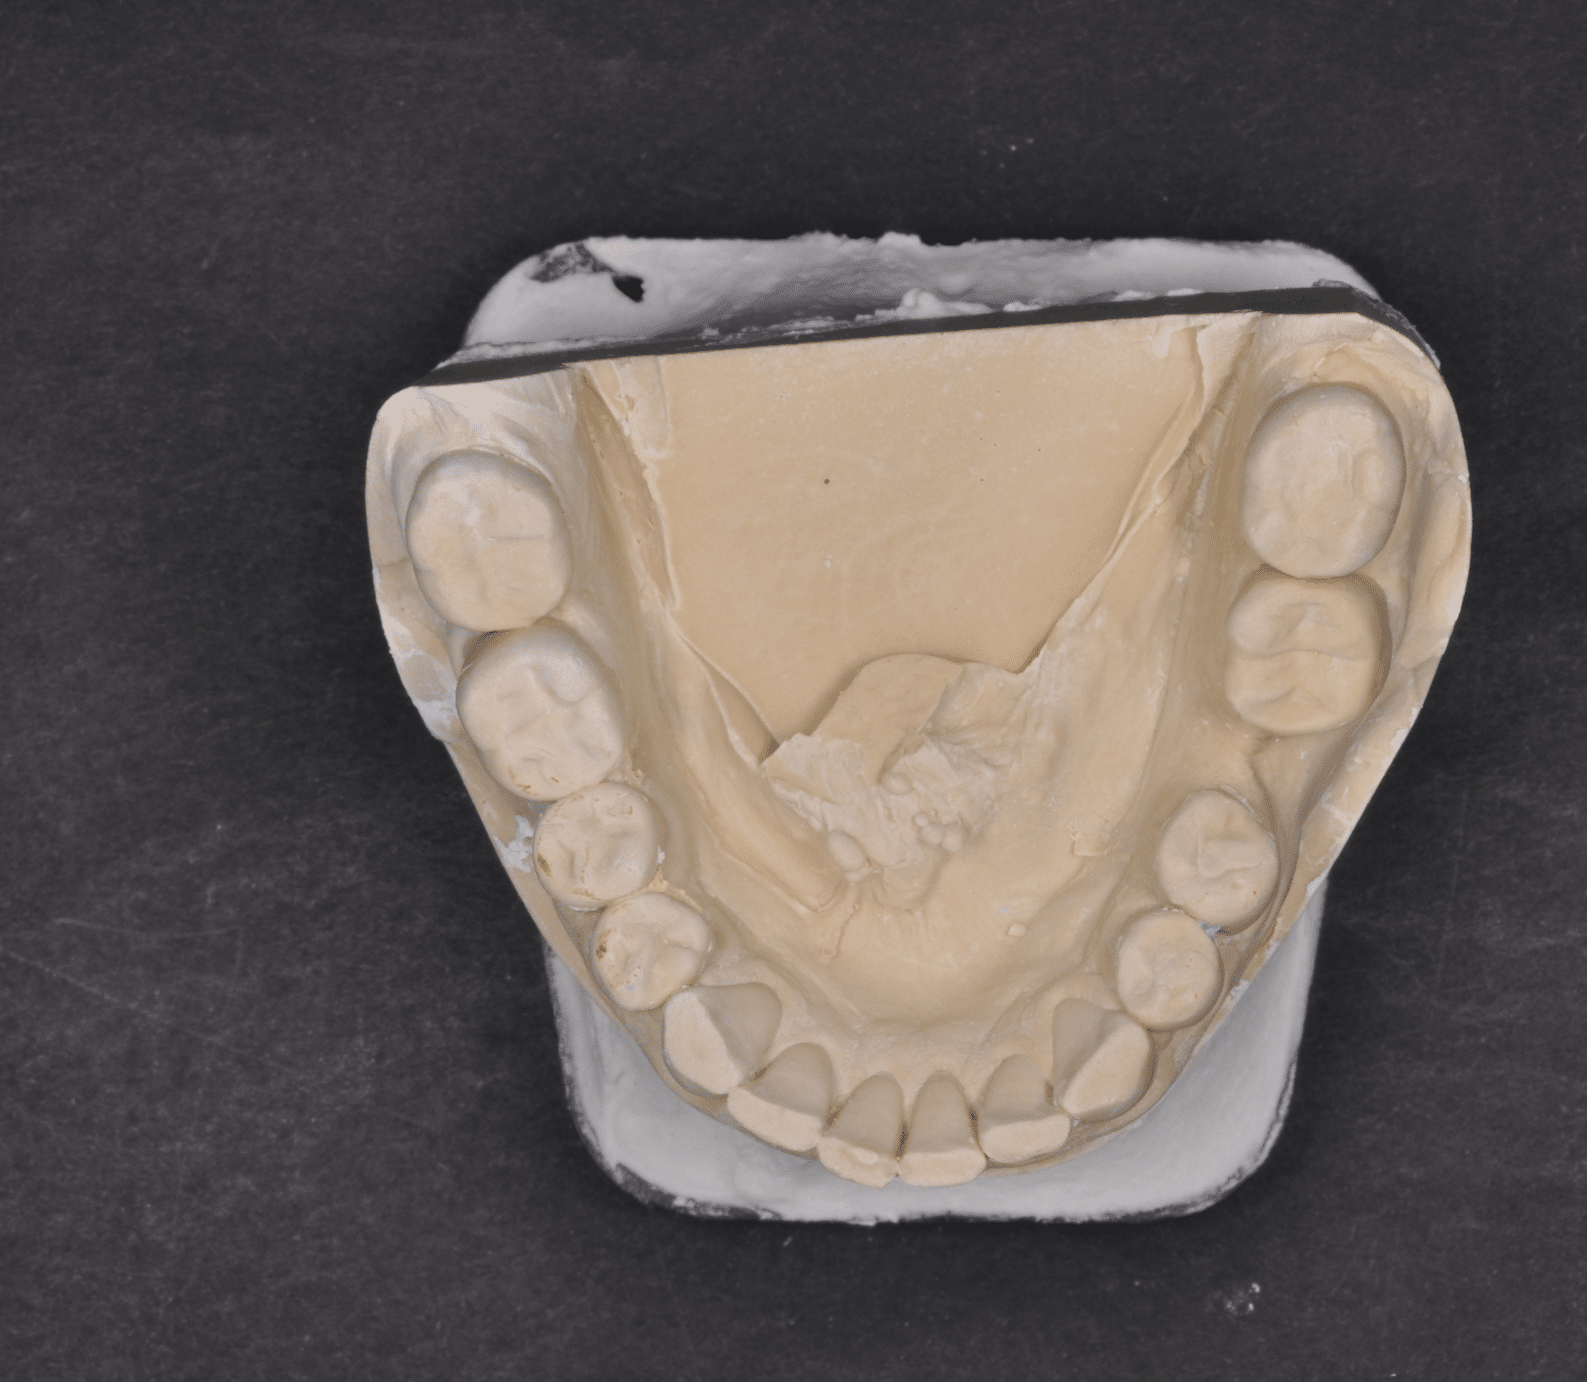

Împreună cu pacientul, am optat pentru inserarea implantelor cu ajutorul ghidului chirurgical pentru a plasa implantul în poziția protetică ideală și pentru a permite realizarea coroanelor insurubate pe implant. A fost efectuată scanarea digitală a arcadelor și a ocluziei pacientului, iar împreună cu tehnicianul radiolog de la DigiRay a fost suprapus fișierul .stl al amprentei digitale peste fișierul .dcm de la CBCT, utilizând software-ul 3Shape.

S-a planificat individual poziția și axul de inserție al fiecărui implant.